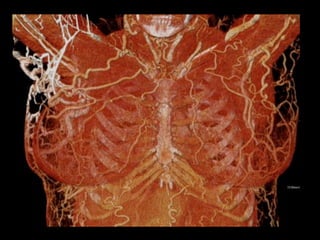

35M hx thighsarcoma. Facial swelling & chest wall varicosities when he bent over to tie his shoes. Documented central venous obstruction. Treatment planning: Assess vascular access, particularly axillary & subclavian veins B/L. Simultaneous bilateral arm injection: 1: 6 dilution (30cc contrast + 170 cc NS, each arm) @ 2cc/sec. Courtesy of Anne Chin, MD

90cc contrast, 60sec diagnostic delay. Imaging range: angle of mandible to lesser trochanters. LT IJV